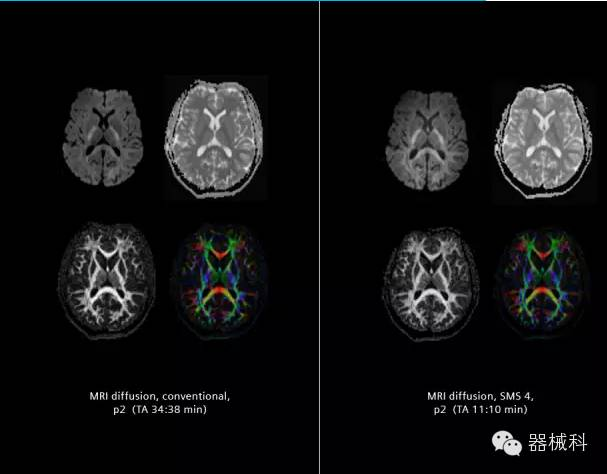

在2015年RSNA上,西門子隆重發(fā)布了Simultaneous Multi-slices 技術(shù)(即同時多層采集技術(shù),簡稱SMS),這是磁共振掃描技術(shù)中第一次引入“同時多層”的概念,此概念技術(shù)的發(fā)布,將對未來磁共振成像領(lǐng)域帶來巨大的變革!

SMS技術(shù)可以將原本用于科研的高級成像技術(shù)轉(zhuǎn)化成臨床常規(guī)。

SMS可以有效提升高級功能成像精準(zhǔn)度。

擁有了SMS“同時多層”采集技術(shù)之后,用戶可以在非常短的時間內(nèi)完成MR掃描,結(jié)合西門子靜音技術(shù),大大提高患者的舒適性,或在單位時間內(nèi)采集更多的數(shù)據(jù),也可以得到高精度、高準(zhǔn)確性、大數(shù)量的功能成像數(shù)據(jù),為臨床和科研提供強大的支持。專家認(rèn)為,SMS“同時多層”采集技術(shù)未來在 提高成像質(zhì)量、外科手術(shù)計劃、降低術(shù)后神經(jīng)功能缺陷、提高fMRI的時間采集效率、提高靜息態(tài)功能磁共振數(shù)據(jù)質(zhì)量等方面將帶來深遠(yuǎn)影響,希望該技術(shù)可以盡早面世,引領(lǐng)磁共振進(jìn)入多層時代!